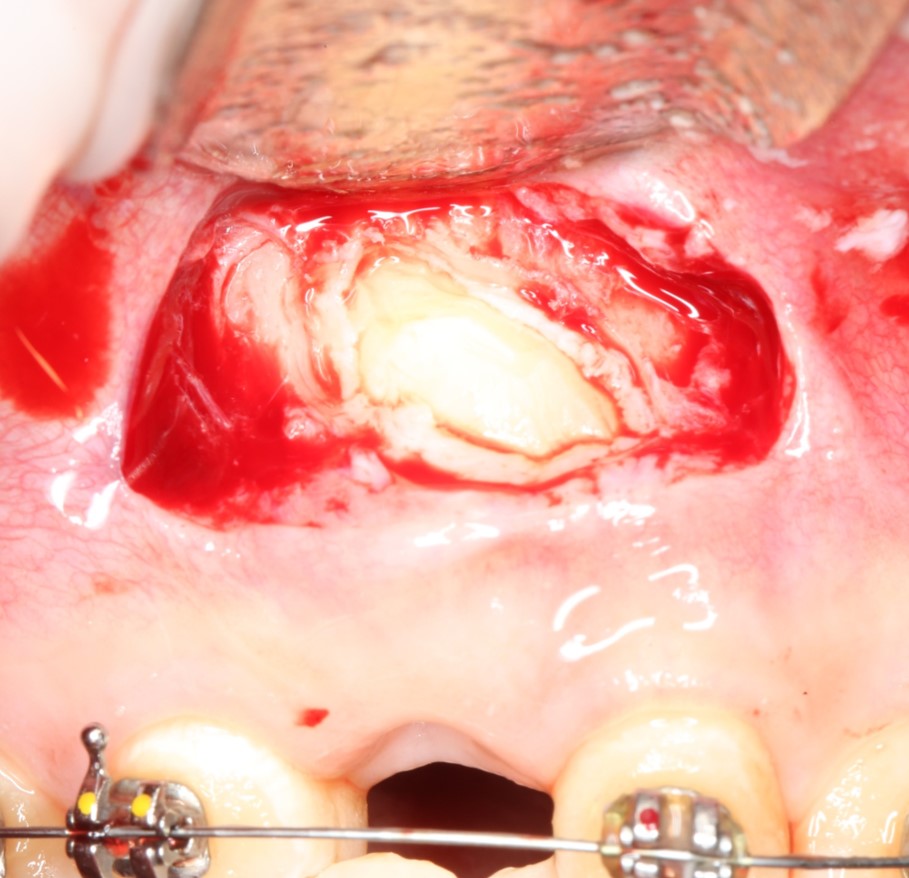

Иссечение воспаленной десны над зубом (того самого «капюшона), с последующей обработкой и дренажем образовавшейся раны.

Такая тактика оправдана в случае, если:

— по данным рентгенодиагностики (КЛКТ или ортопантомограммы) зуб находится в стадии прорезывания (верхушки корней не сформированы), ось прорезывания зуба имеет более-менее правильное направление, его коронковая часть не повреждена кариесом.

— врач-ортодонт подтверждает, что для прорезывания третьего моляра есть необходимое пространство (хватит места в зубном ряду), нет патологии прикуса и признаков развивающейся зубочелюстной аномалии.

— подобное состояние (перикоронит) у тебя впервые, и ты раньше никогда с ним не сталкивался.

— тебе не больше 20 лет.

При совпадении всех четырех условий, КОМПЕТЕНТНЫЙ хирург-стоматолог с помощью скальпеля иссечет десну над коронковой частью прорезывающегося зуба, остановит кровотечение, дренирует образовавшуюся рану, сделает послеоперационные назначения (как правило, они включают в себя антибактериальную и противовоспалительную терапию, а также уход за областью послеоперационной раны) и запишет тебя на послеоперационные осмотры, которые ни в коем случае нельзя игнорировать.